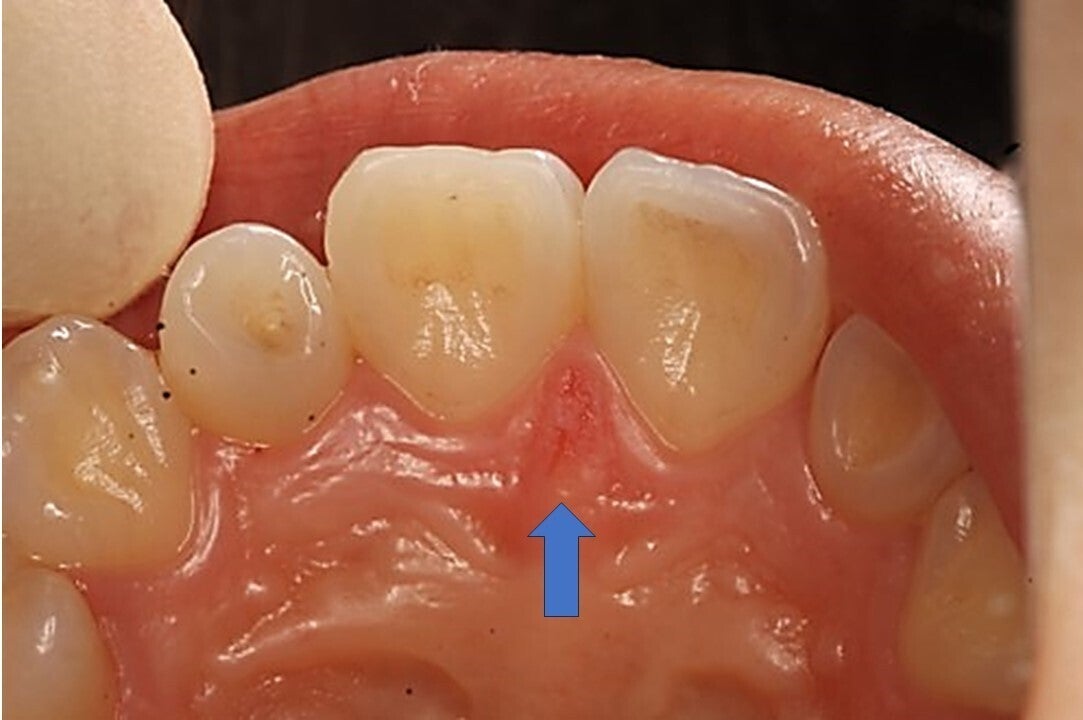

歯ブラシが原因と思われる傷

自分では見えない部分 やり過ぎになってしまう

開業以来、日々の診療の中で、磨き過ぎが原因と考えられる方が多数、来院されます。虫歯も無い、歯周病も無い、しかし、違和感や症状を訴える方がたくさんいらっしゃいます。

よく観察すると、歯ぐきに小さな傷があり、磨き過ぎが原因ではないかと考えました。それから辛抱強く歯みがき指導を行っていくと、大きな処置をしなくても、症状が軽減される方が増えていきました。

着色を取ろうとして毎日磨いたため